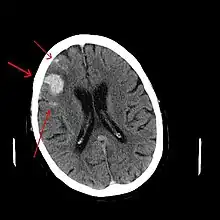

Contusiones

Las contusiones se encuentran en 20% al 25% de los pacientes con TCE grave. Son lesiones heterogéneas compuestas de zonas de hemorragia puntiforme, edema y necrosis que aparecen en las imágenes de TC como áreas de hiperdensidad puntiforme (hemorragias), con hipodensidad circundante (edema), suelen estar localizadas en la cara inferior del lóbulo frontal y la cara anterior del lóbulo temporal por su relación con el ala mayor del esfenoides. También se pueden encontrar en la superficie de impacto y en la superficie contraria a este, el llamado efecto golpe-contragolpe. Cuando estas evolucionan se parecen más a los hematomas intracerebrales y su ubicación depende el posible efecto de masa.